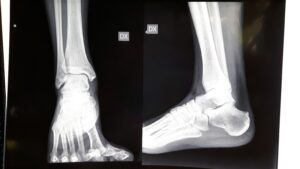

Fig. 1 Rx della patologia

L’alluce varo è una deformazione poco frequente in cui il primo dito del piede risulta deviato verso l’interno (l’altro piede) di pochi gradi fino ad arrivare a 80. A volte coinvolge solo la prima falange, spesso coesiste rotazione esterna dell’alluce che può essere di grado più o meno elevato.